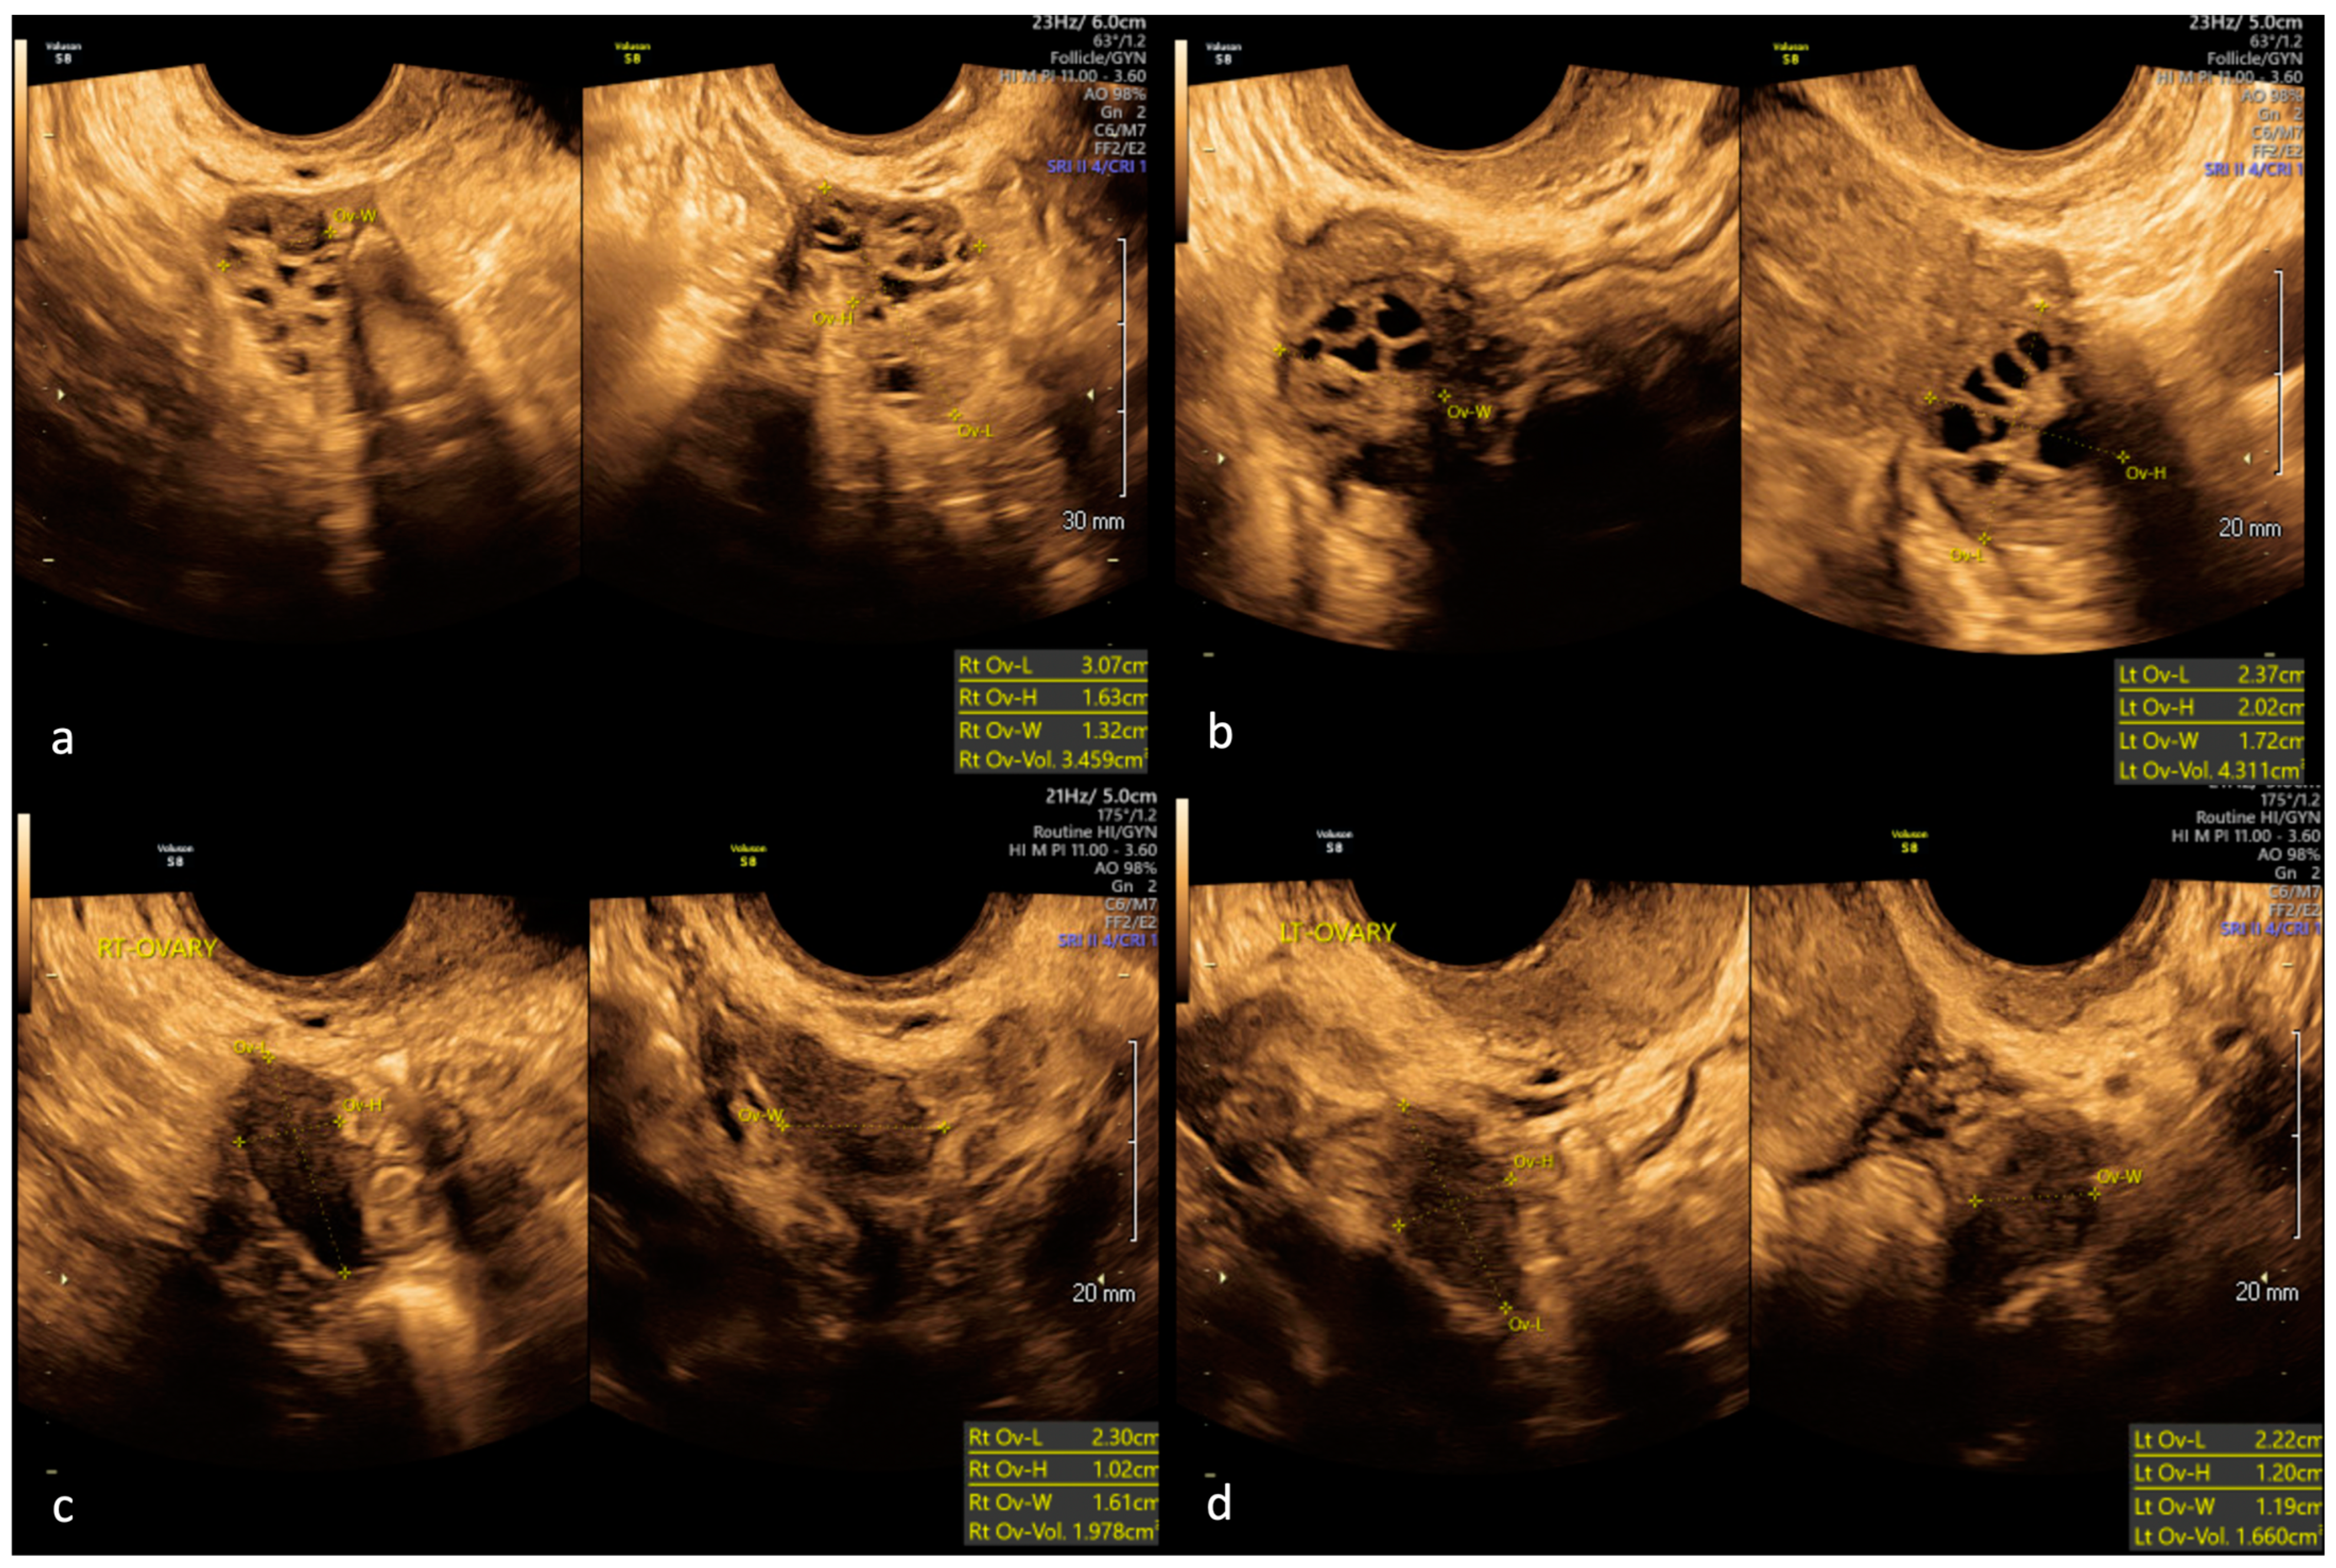

2. Case Report